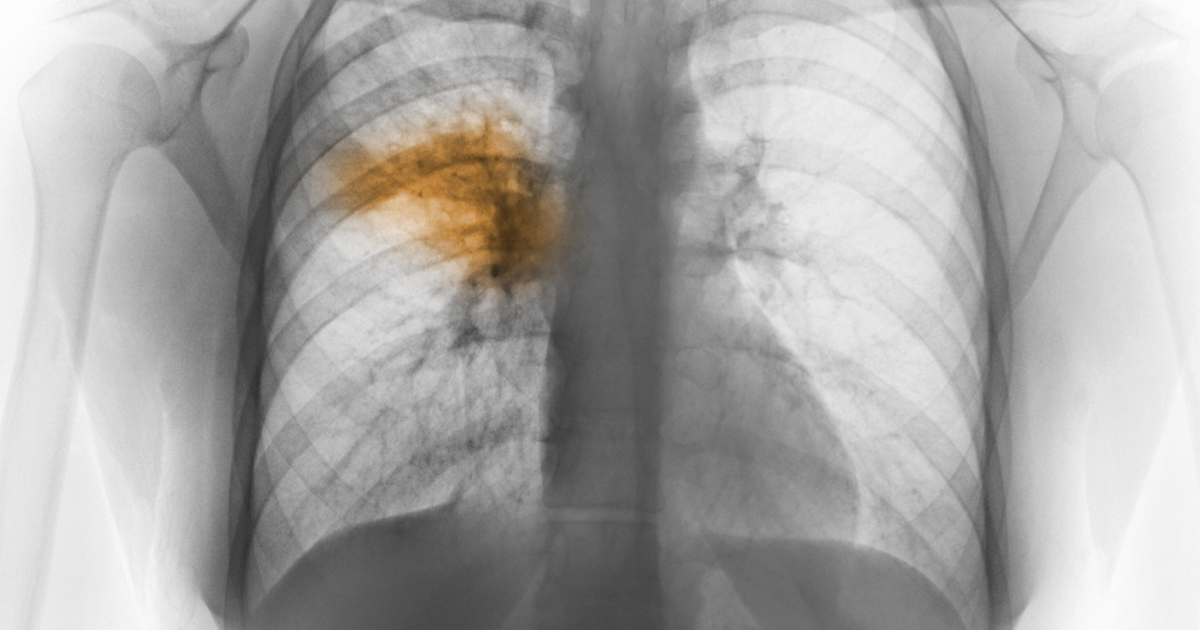

Рентгенодиагностика бронхопневмонии: Советы и примеры